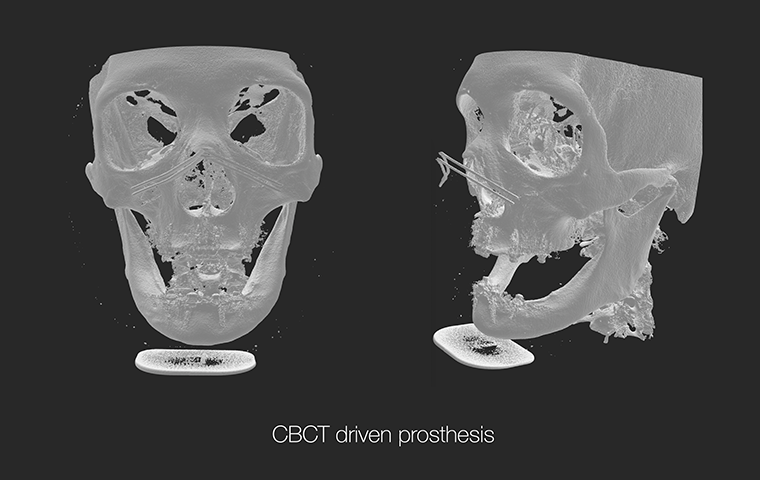

All-on-X

Practical Digital Prosthodontics: Understanding and applying

All-on-X treatment concept

Dr. Janghyun Paek

Professor at Kyunghee University, Department of Prosthodontics

All-on-X

Dr. Janghyun Paek

|

Practical Digital Prosthodontics: Understanding and Applying All-on-X Treatment Concept |

All-on-X

Dr. Janghyun Paek

|

Practical Digital Prosthodontics: Understanding and Applying All-on-X Treatment Concept |

Special Pre-Day Course

Practical Digital Minimalism

Dr. Janghyun Paek

Explore the digital implant dentistry, including the All-on-X treatment concept, guide surgery, immediate loading protocols, prosthodontic considerations, and soft tissue contouring. Course also includes hands-on for All-on-X implant placement, prosthodontic components, intraoral scan, and immediate loading.